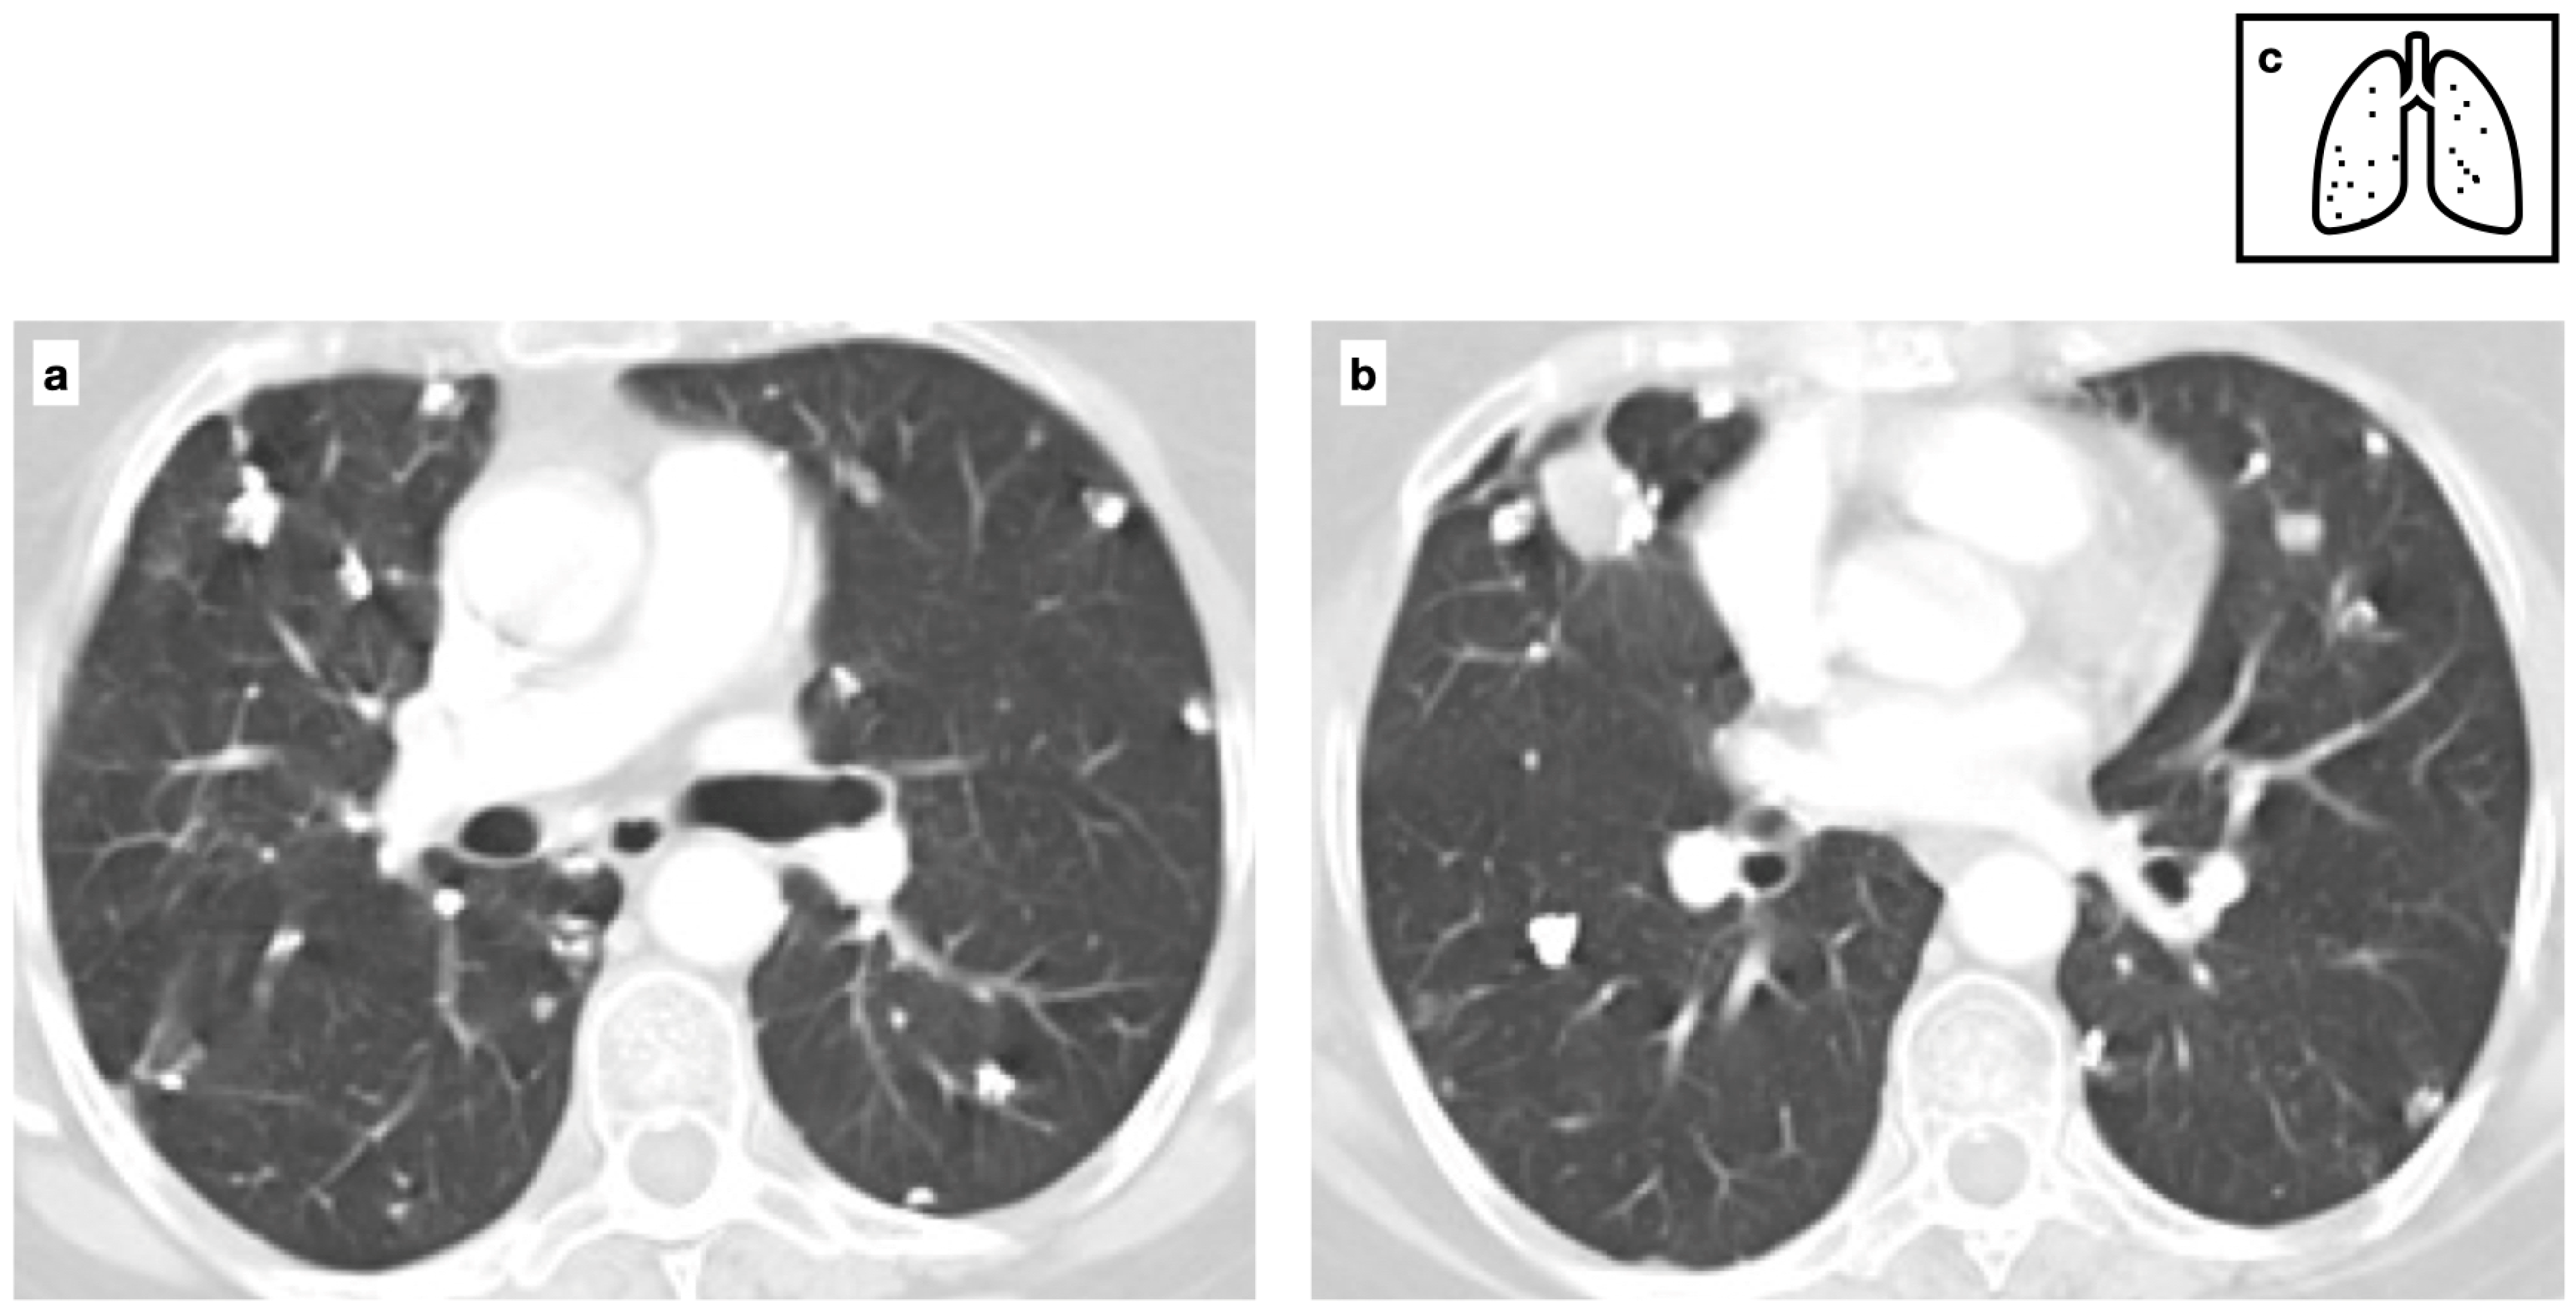

Figure 5.

Patient with previous history of severe varicella pneumonia. HRCT shows bilateral diffuse ill-defined calcified nodules. Scattered diffuse micronodular calcifications are an uncommon late sequela of VZV pneumonia (a,b). Pattern of calcification (c).